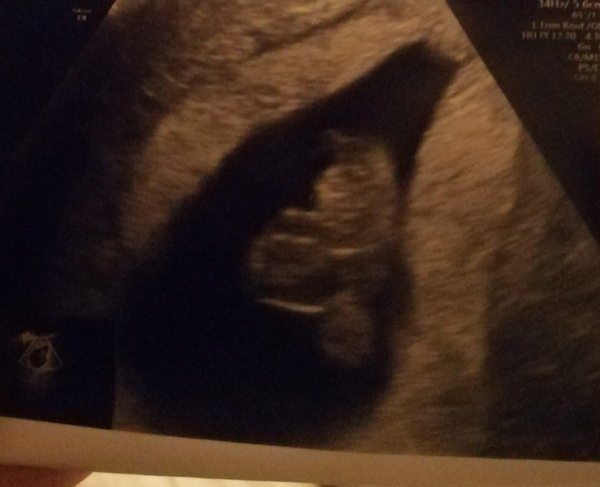

Thank you for all your support in the torturous wait for my scan. Very shocked to see a foetus measuring 8 weeks exactly with a strong heartbeat. There's a haemorrhage beside the baby's sac in the womb, it seems to be an old one and is healing in parts. This is basically the best outcome I had envisioned for there being an actual baby in there, from the type of bleeding I've been having for the last 2 weeks it seemed some bit likely, if it wasn't a miscarriage.

I'm back in 2 weeks for another scan to check it, and on progesterone until about 16 weeks.